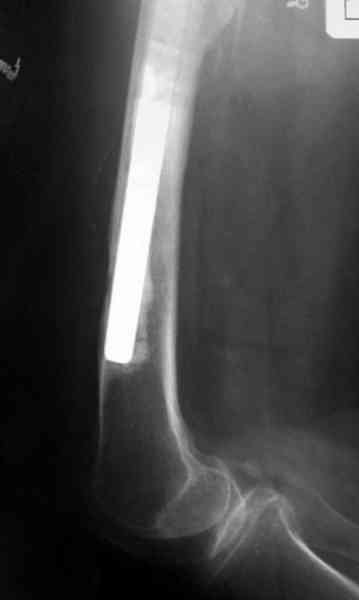

Для спейсера в бедро использовал старый длинный бедренний компонент меньшего диаметра, облепленный со всех сторон цементом с антибиотиком.

№3-6 снимки с осложнением

и последние снимки.